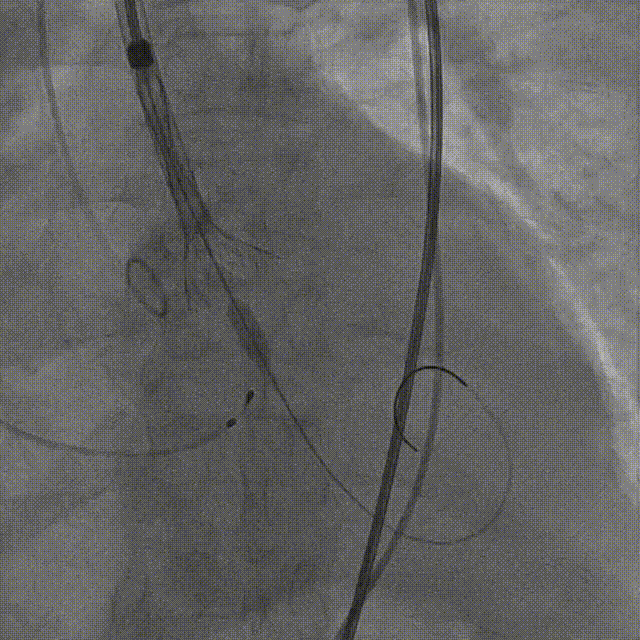

手术影像:

输送器柔顺过弓、跨瓣

瓣膜开始零位定位

瓣膜逐步释放到工作位

工作位造影位置良好

瓣膜逐个脱钩

完全释放后造影,膨胀不良,有漏

25mm球囊后扩

后扩后瓣膜形态良好,造影基本无漏